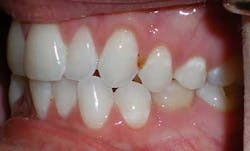

A 27-year-old female presented with a chief complaint of crowding on the upper and lower arches. Upon evaluation, it was noted that the patient had 2 mm and 4.5 mm of maxillary and mandibular arch length deficiency respectively, a missing lower left second bicuspid with primary tooth still present, small upper lateral incisors, cross-bite of the lower right canine, and lower midline shift to the right of 2 mm. (Figs. 1-8)

Figs. 1-8